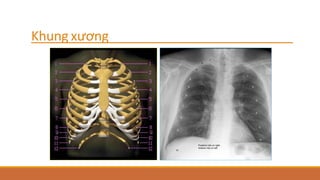

2/ Xương lồngngực

- Xương sườn

- Xương ức

- Cột sống ngực

- Xương vai

- Xương đòn

Khung xương

Bờ dưới xương sườn

Bờ dưới xương sườn vùng giữa và thấp dạng dải mờ (tránh lầm phản ứng màng xương)

Đầu xương sườn phía sau khớp vào thân

sống và mỏm ngang 

tránh lầm gãy